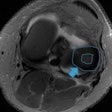

PET/MRI effectively diagnoses foot pain